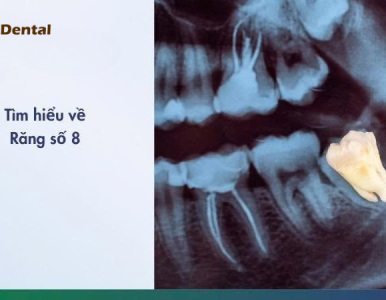

Răng khôn (răng số 8) thường mọc lệch, mọc kẹt gây đau, viêm nhiễm và nhiều biến chứng nguy hiểm. Cùng Nha Khoa SV tìm hiểu khi nào nên nhổ răng khôn an toàn.

Tìm hiểu dấu hiệu răng khôn mọc lệch, mức độ nguy hiểm và cách xử lý an toàn. Bài viết cung cấp thông tin đầy đủ, kèm video thực tế tại Nha Khoa SV.

Tìm hiểu răng số 8 (răng khôn), dấu hiệu mọc, các dạng nguy hiểm và phương pháp nhổ răng khôn chuẩn y khoa tại Nha Khoa SV.